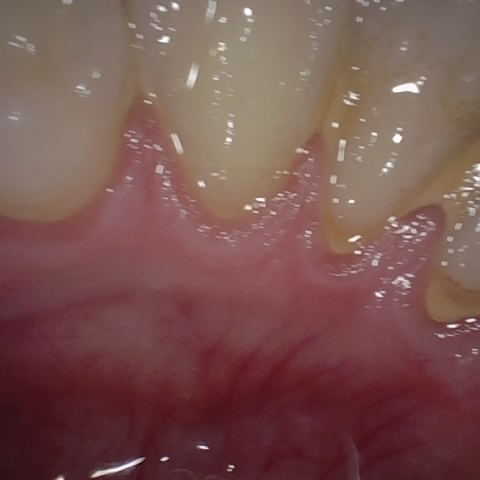

Annotated as "Bad"